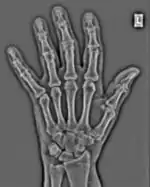

FFTs can also be calculated in two-dimensions to give results such as those in Figure 1.27. Since Fourier analysis generates results in terms of both positive and negative spatial frequencies, these can be plotted in the form of a 2D image so that the maximum frequency lies at the origin and those for the horizontal and vertical directions are shown increasing towards that origin. The modulation at different spatial frequencies is represented using a grey-scale. Low frequency bands can be seen along the horizontal axis in the figure, for example, representing the horizontal periodicity of image data from the fingers, while finer bands along the y-dimension are indicative of a periodicity of image data from the various metacarpophalangeal joints. Higher frequency features can also be seen running diagonally in this 2D-FFT, representative of the trabecular structure of the bones, for example.

The essence of this approach is that it can be used to produce a range of image processing effects by enhancing and/or suppressing features in the 2D-FFT and then converting the result back into the spatial domain using the IFT, as illustrated in Figure 1.28. Such image manipulations are considered in more detail in a later chapter. Note that the form of image processing demonstrated in the figure is for purely illustrative purposes and bears no direct medical significance.

![]() Fig. 1.28(a): A radiograph of the wrist. | ![]() Fig. 1.28(b): The wrist radiograph processed by attenuating periodic structures of size between 1 and 10 pixels. |